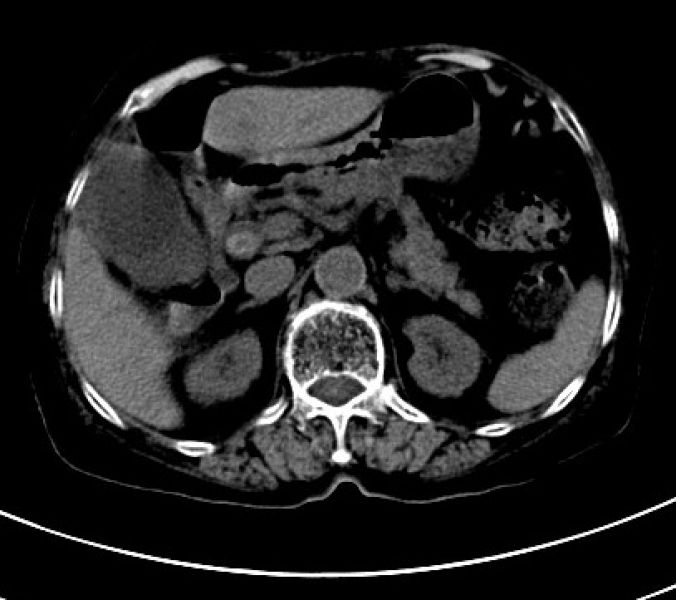

术前增强CT结果